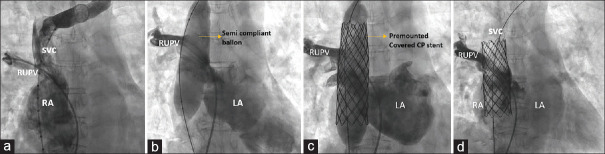

Superior vena cava (SVC) type of sinus venosus defect (SVD) associated with anomalous right upper pulmonary vein (RUPV) drainage is often corrected by open-heart surgery. Transcatheter-covered stent exclusion is an attractive emerging alternative using a covered stent in the lower end of SVC to close the SVD and redirect the RUPV to the left atrium. The location of SVD posterosuperior to oval fossa challenges its transthoracic echocardiographic identification and delays its diagnosis to adult age. Lifestyle adult diseases, including atherosclerosis, elevate the left ventricular end-diastolic pressures and increase the pretricuspid left-to-right shunt. Surgery addresses coronary stenosis and SVD, but lifestyle diseases increase surgical risks. We diagnosed significant coronary stenosis in three patients with SVD. These patients underwent percutaneous management of both lesions. Nonsurgical management of SVD and ischemic heart disease is a more viable alternative than a high-risk surgery in adults with comorbidities.